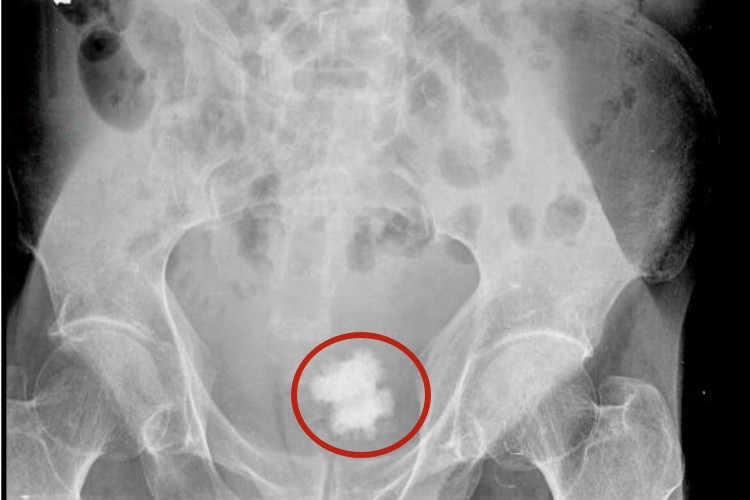

膀胱结石

膀胱结石的典型症状为排尿突然中断并出现疼痛,可放射至远端尿道及阴茎头部,伴有排尿困难和膀胱刺激症状,小儿常用手搓拉阴茎。跑跳或改变排尿姿势后能使疼痛缓解,可继续排尿。